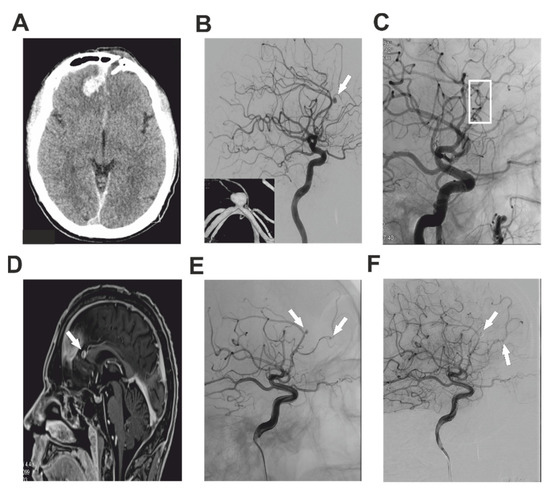

2.1. Case Report 1

2.2. Case Report 2